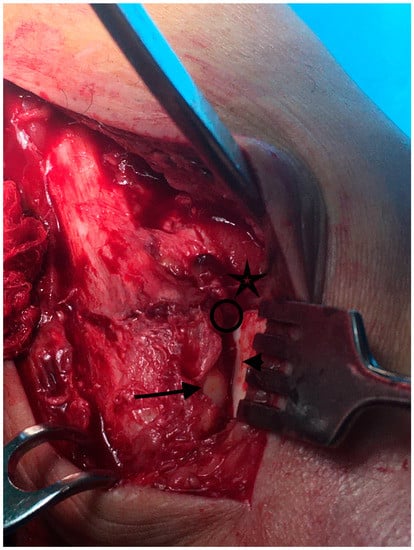

- The superior lateral malleolus cartilage was aligned with the anterolateral tibial plafond cartilage (restoring the fibula length) (Figure 2):